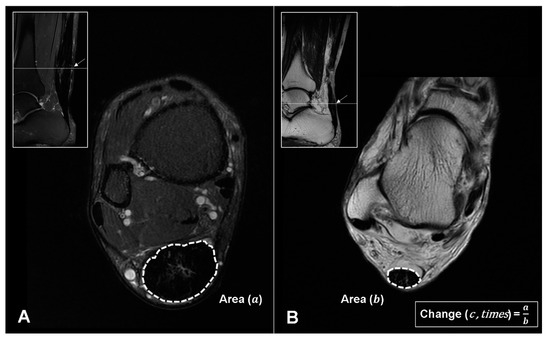

2.5.2. Fat-Saturated T2-Weighted Axial Image

| Postop circumferential area changes (times) | 2.43 ± 0.41 | 3.19 ± 0.51 | 0.0012 |